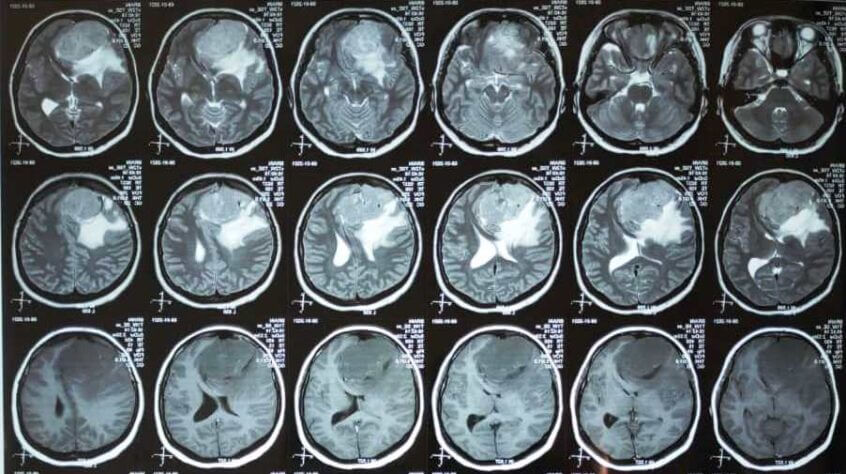

С 15 по 16 января 2021 года проректор КГМА им.И.К.Ахунбаева, профессор-нейрохирург Кенешбек Ырысов по линии санитарной авиации провел сложнейшие операции трем пациентам с гигантскими опухолями головного мозга в отделении нейрохирургии Ошской межобластной объединенной клинической больницы. Операция прошла успешно, пациенты пришли в себя без неврологического дефицита и каких-либо других осложнений.